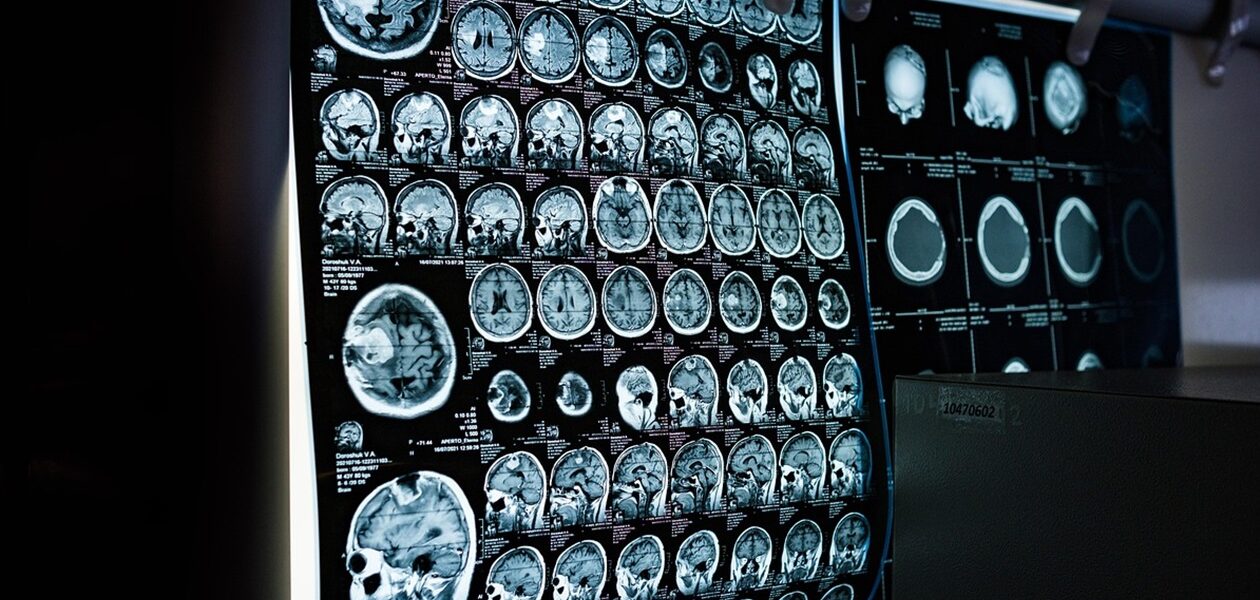

Зміни у зовнішності, включно з набряками губ, збільшенням пальців і ширшим обличчям, тривалий час списували на стрес. Після переїзду до Нью-Йорка стан погіршувався, і лише у приватній клініці в Колорадо після МРТ та аналізів встановили правильний діагноз: рівень гормону росту у Седорік був утричі вищим за норму, а на гіпофізі виявили 1,4-сантиметрову макроаденому.